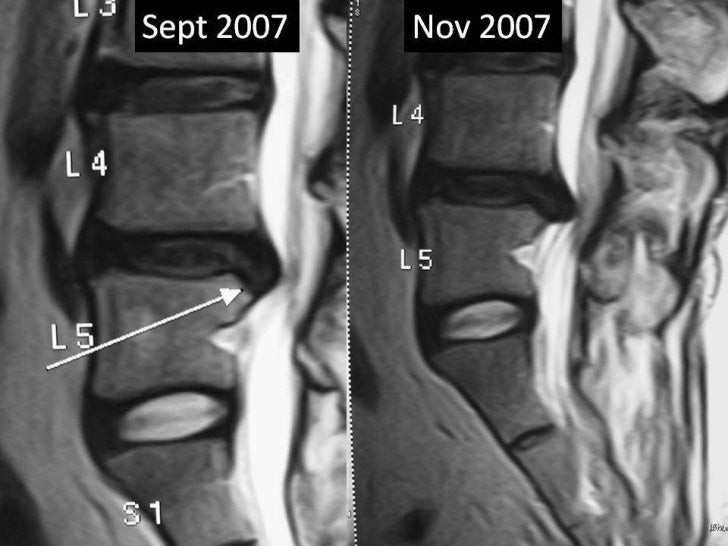

From www.slideshare.net

Lumbar disc extrusion recurrence Lumbar Disc Extrusion Icd 10 Identify the etiology of lumbar disc herniations. m51.26 is a diagnosis code for other intervertebral disc displacement in the lumbar region. Review the proper steps in the evaluation of lumbar disc herniations. It is billable and effective from. m51.27 is a billable code for other intervertebral disc displacement in the lumbosacral region. m51.16 is a specific code. Lumbar Disc Extrusion Icd 10.